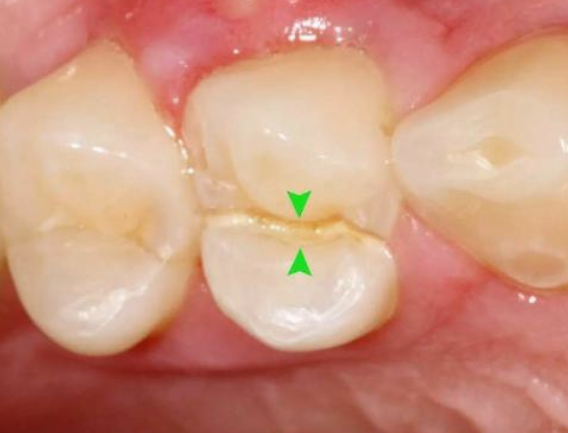

于是抱着侥幸心理,让牙齿在没有“防护衣”的情况下:咬着小坚果,嗑着小瓜子……有一天,“咔”!牙齿劈裂了!

根管治疗是针对牙髓炎或牙髓坏死、根尖病变不能保留活髓的折裂牙,进行治疗的有效方法。

根管治疗后及时戴冠,这种建议是从有利于患者的角度提出的!从医学专业角度来说,戴冠修复也是根管治疗的必要步骤!

7、根管打桩:因牙体缺损过多,导致牙的强度(承受力量的性能)大幅度下降,不能很好地承受咀嚼力量。打桩的目的是增加牙根及牙冠的强度,增加患牙的稳固。

8、完成牙体修复:X线片显示根管充填完好,行暂时或永久牙体修复,带上牙冠,保护患牙。至此根管治疗才可算完成,同时根管治疗后还需复诊,一般周期可为3个月、半年、1年、2年或更长。